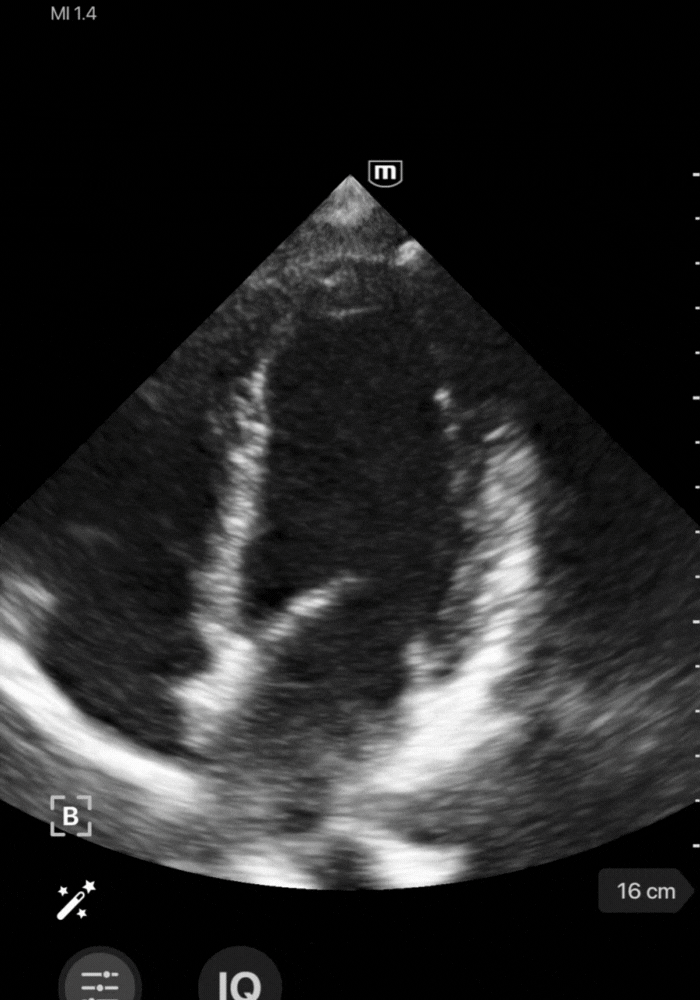

Parasternal petit axe → Cinétique pariétale

En parasternal petit axe, identifiez les anomalies de la cinétique pariétale en recherchant une asymétrie de contraction entre les différents segments du ventricule gauche. A noter que la contraction concentrique du VG est symétrique et harmonieuse, chaque segment se rapprochant de façon égale du repère circulaire central (video ci-dessous).